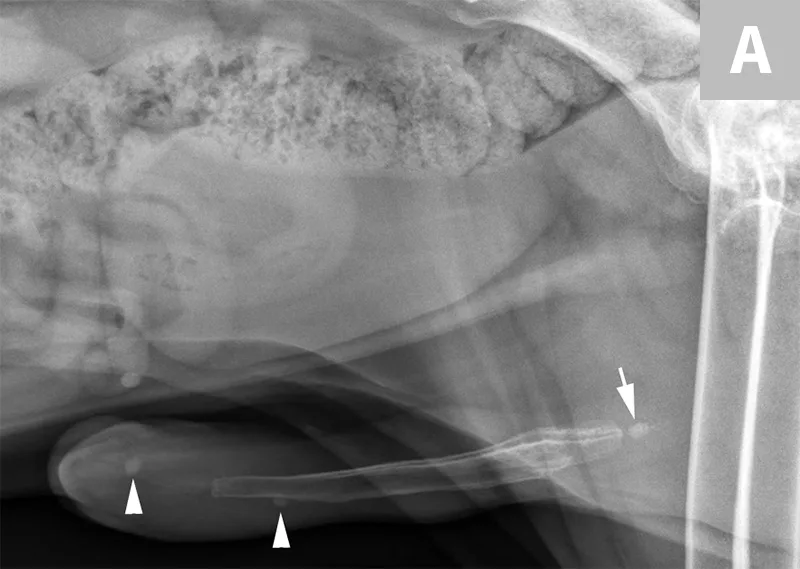

Lateral x-ray of caudal aspect of dog with arrows pointing to radiopaque objects in penile urethra.

FIGURE 10

Lateral radiograph of a male dog centered on the perineum with the pelvic limbs pulled ventrally (flexion of the pelvis at the coxofemoral joints). This radiograph documents multiple well-defined, mineral opaque calculi within the penile urethra (arrows).

A separate center of ossification associated with the os penis may mimic a urethral calculus (Figure 11 A and B). A separate center of ossification can be seen at either end of the os penis and will be in line with the os penis. A calculus within the penile urethra would be seen ventral to the os penis in the location of the urethra. Contrast urethrography can be a helpful way to differentiate between a separate center of ossification and urethral calculus (Figure 11C).

FIGURE 11A

Lateral radiograph of a male dog collimated to include the urinary bladder and os penis. Note the well-defined mineral opacity just proximal to and at the same level as the base of the os penis—a separate center of ossification (arrow). Also note the two soft tissue opaque nodules summating with the prepuce, presumed to be small nipples (arrowheads).